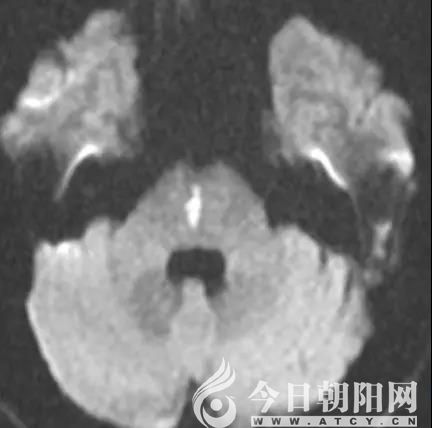

患者術(shù)前磁共振影像

患者術(shù)后磁共振影像

9點(diǎn)30分,孟昭民、宋鳳芝兩位主任帶領(lǐng)神經(jīng)內(nèi)科二區(qū)、急診腦卒中小組相關(guān)人員對(duì)患者進(jìn)行了相關(guān)檢查;9點(diǎn)45分,患者臨床癥狀持續(xù)了一小時(shí)沒(méi)有緩解,于是給予相應(yīng)藥物治療;9點(diǎn)55分,影像結(jié)果顯示患者出現(xiàn)腦干梗死,如果不能及時(shí)挽救病變區(qū)的腦組織,死亡的幾率很大,即使不死亡,也會(huì)遺留嚴(yán)重的后遺癥。靜脈溶栓藥物已經(jīng)完全進(jìn)入體內(nèi),患者依舊沒(méi)有恢復(fù),腦干梗死癥狀仍存在;10點(diǎn)30分,患者的病情再一次惡化。由于患者做頭磁共振血管造影(MRA)時(shí)有陣發(fā)性震顫,所得影像并不理想,再次和家屬溝通后,決定實(shí)施全腦血管造影(DSA),如果造影顯示大血管閉塞,可以直接機(jī)械取栓治療,為急診介入超早期治療爭(zhēng)取更多時(shí)間;11時(shí)30分,造影顯示雙側(cè)頸總動(dòng)脈、頸內(nèi)動(dòng)脈、雙側(cè)椎動(dòng)脈及基底動(dòng)脈等大血管未見(jiàn)閉塞性改變,不需要采取機(jī)械取栓;下午1點(diǎn)30分,患者蘇醒后,神經(jīng)定位體征完全消失,意識(shí)恢復(fù)清楚,四肢活動(dòng)自如,且能夠自由交流。